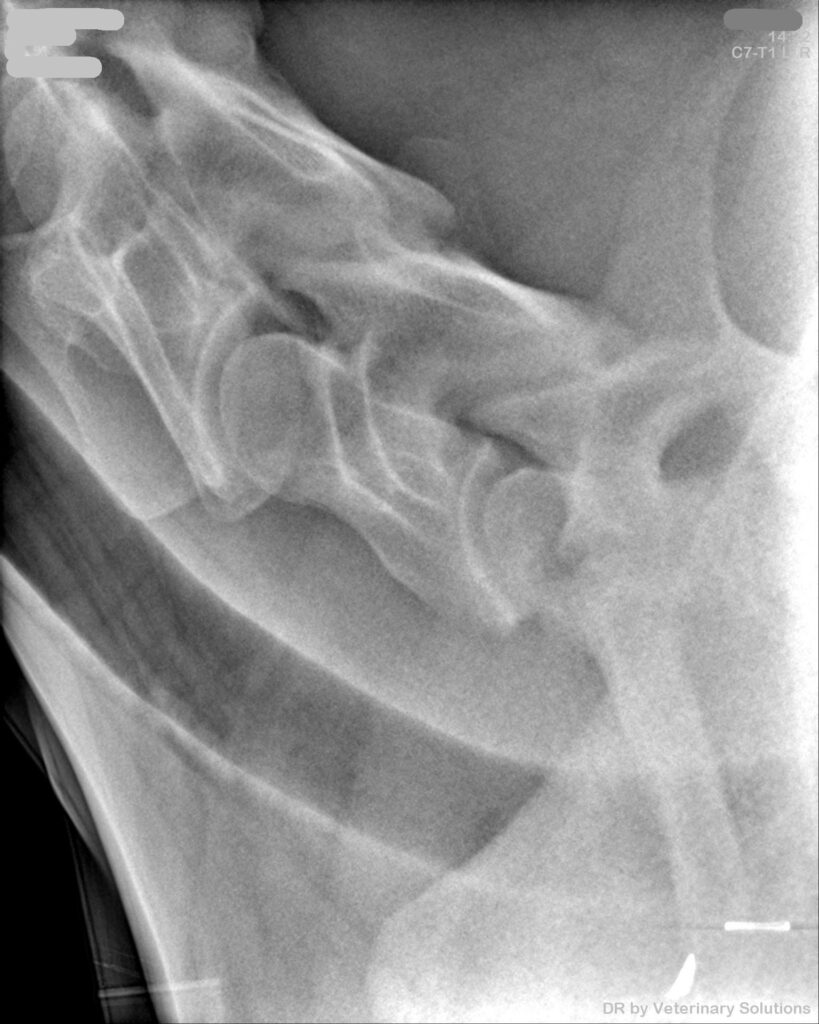

Ultraschall, Röntgen, JETZT auch Endoskopie

Ultraschall, Röntgen